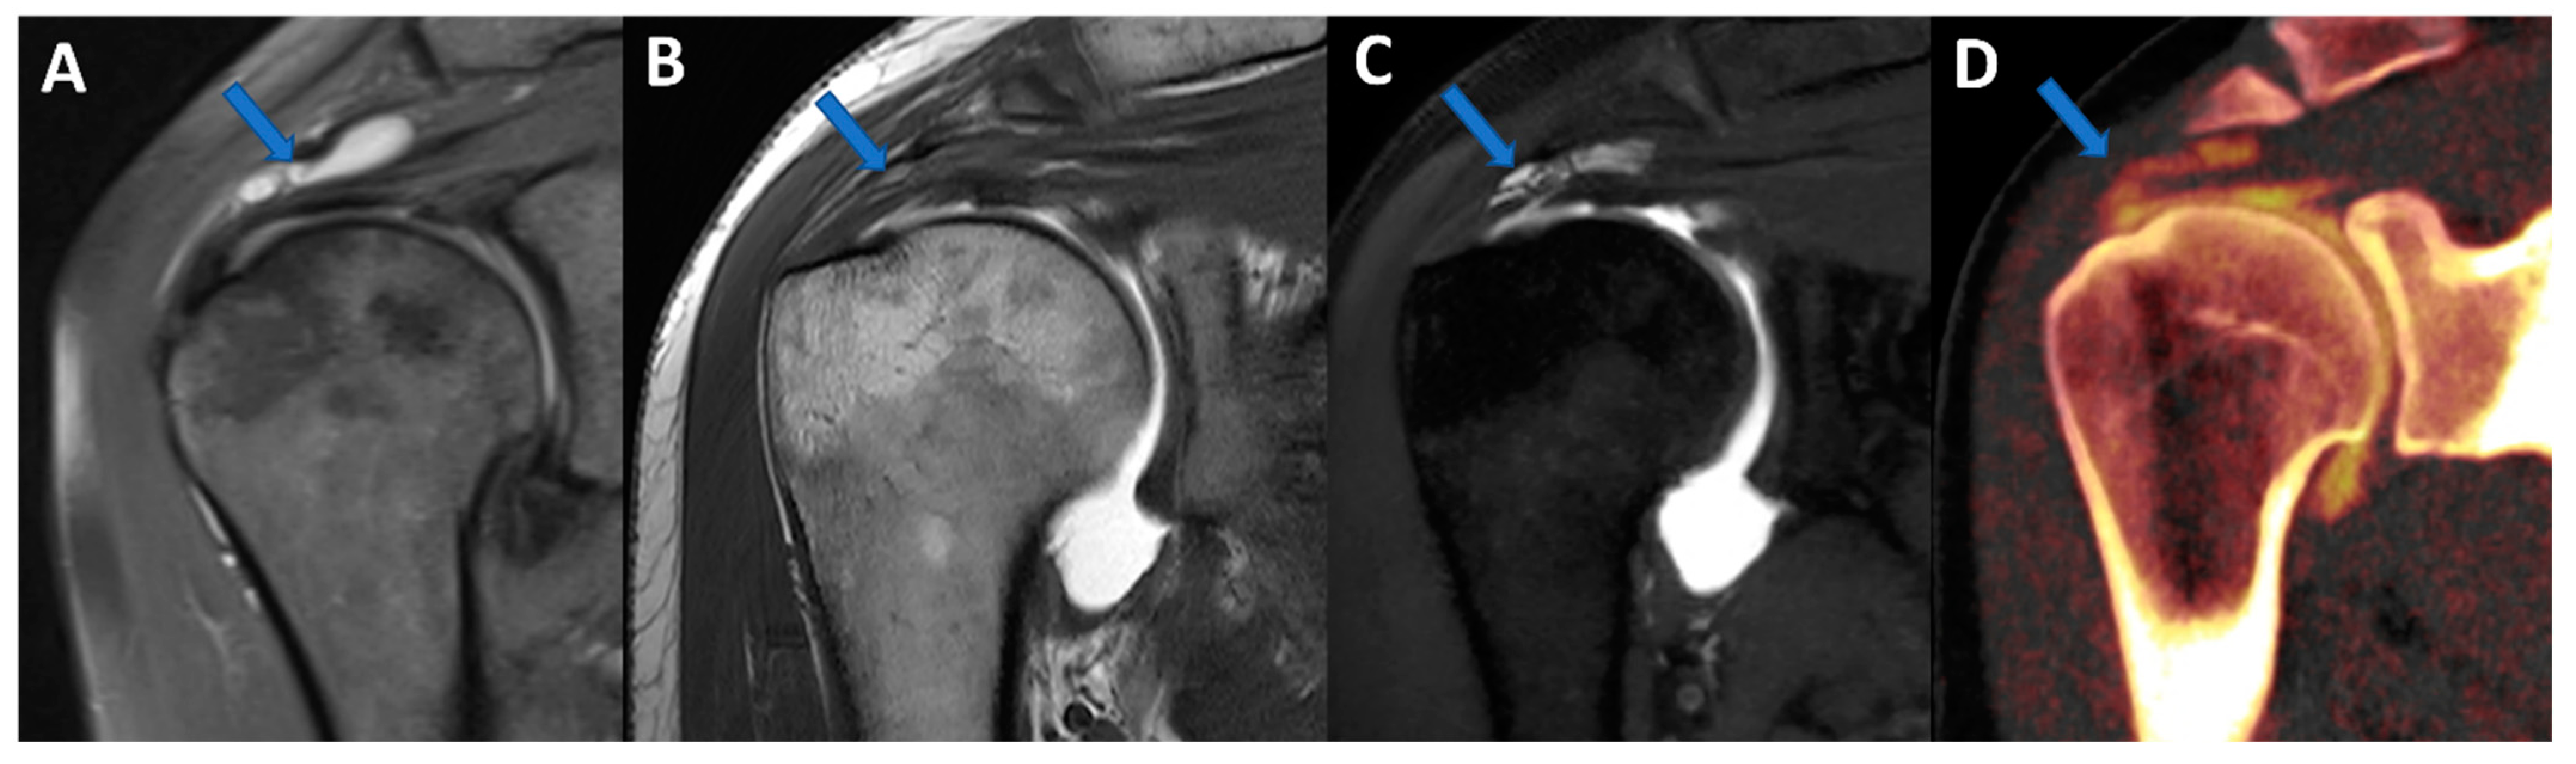

Figure 4. Complete supraspinatus tendon diagnosed using DECTA. On the coronal standard STIR MRI image (A), a fluid collection located on the bursal side of the supraspinatus tendon can be identified (arrow). On the coronal T1 weighted TSE MRA image (B), the supraspinatus tendon appears irregularly thinned, as in a case of a partial tear. There is no apparent passage of contrast material on the bursal side (arrow). On the corresponding 1 mm PD fat-saturated image of the coronal plane (C), there are still no clear signs of complete tendon tears (arrow). The reconstructed DECTA 1 mm coronal image (iodine map; (D)) clearly demonstrates the presence of a complete tear with the passage of contrast material on the bursal side of the tendon (arrow).

Iodine maps have been largely employed in body and vascular imaging to increase the contrast among soft tissues because iodine maps enhance the signal coming from iodine contrast [20,21,22,23]. In a recently published paper [5], DECTA of the shoulder was superior in the detection of glenoid labrum and rotator cuff tears with respect to standard CTA (sensitivity rose from 84.2% to 92.1% for reader 1; specificity rose from 77.8% to 88.9% for reader 2). Conversely, intra-observer agreement was higher for CTA if compared to DECTA [24]. In clinical practice, iodine maps can be used to enhance the visualization of tiny, subtle tears by modulating the vividness of contrast material, with a subsequent increase in contrast within soft tissues, including articular cartilages (Figure 4). The possibility of modulating the signal from injected contrast material may be very useful in cases of difficulty injecting contrast material in the articular cavity. For example, the signal can be augmented in cases of diluted or small amounts of injected contrast material or in cases with pre-existing intra-articular fluid. Conversely, the signal from injected contrast material could be reduced in the case of poorly diluted contrast material, causing artifacts that may obscure the adjacent bony or soft tissue structures. Additionally, in clinical practice, the signal coming from contrast material can be changed depending on the radiologist’s choice of non-destructive flow.